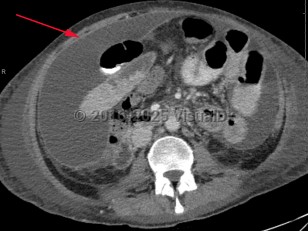

Inflammation of the visceral and parietal peritoneum resulting in acute, severe abdominal pain with fever and diffuse abdominal tenderness with rigidity and guarding, most often secondary to an infectious or inflammatory process. Peritonitis can be primary, secondary, or a result of continuous peritoneal dialysis:

- Secondary peritonitis – Results from the contamination of the peritoneum from spillage from an intraabdominal viscus, and results in gradually worsening abdominal pain as the parietal peritoneum becomes irritated. Pain, fever, and guarding are common presenting symptoms. Polymicrobial infections are common, including gram positive, gram negative, and anaerobes.